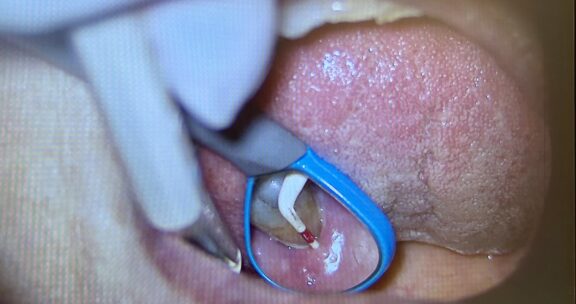

下の写真は、実際にマイクロスコープを使用して 歯周ポケットを測定している場面です。

プローブ(細い器具)を歯と歯ぐきの間に挿入し深さをミリ単位で測定します。

◎拡大視野で確認

肉眼では見えにくい歯石や炎症の状態を、マイクロスコープで細かくチェックできます。

◎出血の有無も確認

測定時に出血が見られる場合は、炎症が起きているサインです。